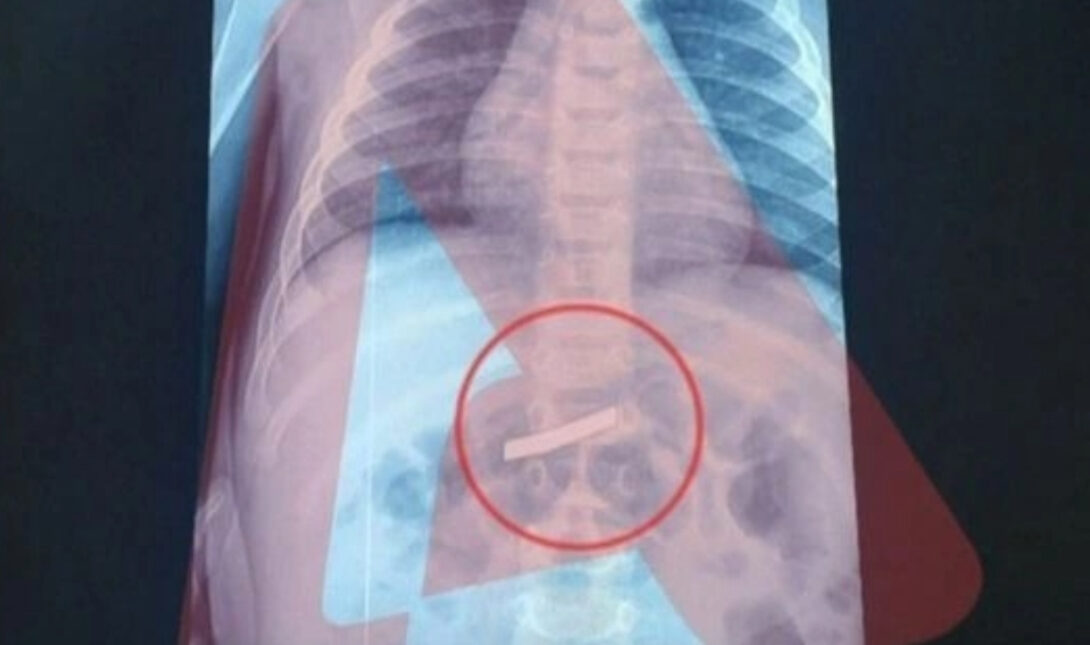

Αίσια έκβαση είχε η περιπέτεια για το τρίχρονο παιδί που κατάπιε ξυραφάκι και μεταφέρθηκε επειγόντως στο νοσοκομείο, όπου υπεβλήθη εσπευσμένα σε χειρουργική επέμβαση για να αφαιρεθεί το επικίνδυνο αντικείμενο.

Το χειρουργείο ήταν πετυχημένο και το μικρό παιδί αναρρώνει πλέον στο σπίτι, καθώς δεν χρειάστηκε να νοσηλευτεί.

- Το τρίχρονο παιδί που κατάπιε ξυραφάκι υποβλήθηκε σε επιτυχημένη χειρουργική επέμβαση και αναρρώνει στο σπίτι του.